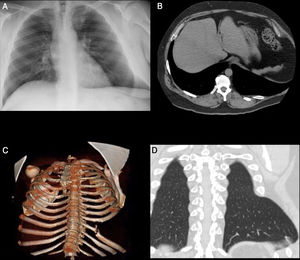

Varón de 51 años que presenta tumoración en región costal izquierda, tras episodio de bronquitis aguda, en relación con hernia intercostal. Se trata de una entidad poco frecuente que por su etiología puede ser clasificada como congénita o adquirida (traumática, posquirúrgica o espontánea). Las hernias espontáneas suelen asociarse a maniobras de hiperpresión (tos) que provocan el desgarro de los músculos intercostales o incluso la fractura de una o varias costillas (fig. 1). Aunque la sospecha es clínica, la tomografía computarizada (TC) es necesaria para confirmar el diagnóstico y planificar la intervención quirúrgica. La reparación protésica sin tensión es el tratamiento de elección.